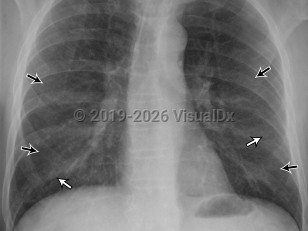

Chest pain, Pleural effusion, 50-59 year old Female

Pleural effusionPleural effusion

Lung cancerLung cancer

Malignant mesothelioma